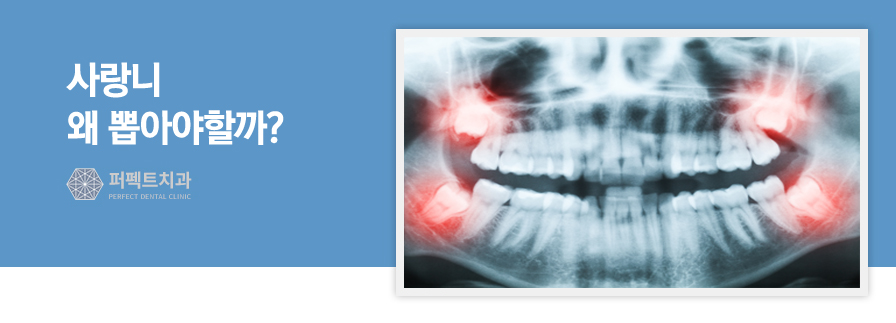

왜 사랑니를 뽑아야 할까?

앞서 언급했듯이, 사랑니는 다른 치아가

이미 완전히 형성된 청년기에 나기

시작하는데요. 많은 사람의 구강에는 사랑니가

나기 시작해 정상적으로 발달하기에 충분한

공간이 없습니다.

따라서 일부 사랑니는 옆에 있는 치아를

누르면서 자랄 수 있죠. 심지어는 구강의

뒤쪽으로 자라거나 턱뼈를 통과하지

못할 수도 있습니다. 이는 잇몸이 감염되고

인접 치아가 손상될 수 있으며

종종 전체 부위에 염증이 생기기도 합니다.

사랑니는 구강의 뒤쪽에 위치해 있으므로,

충치가 생기거나 음식물이 끼는 것이 매우

일반적입니다. 이 모든 측면으로 인해,

사랑니는 그대로 두는 것보다

뽑는 것이 더 좋습니다.